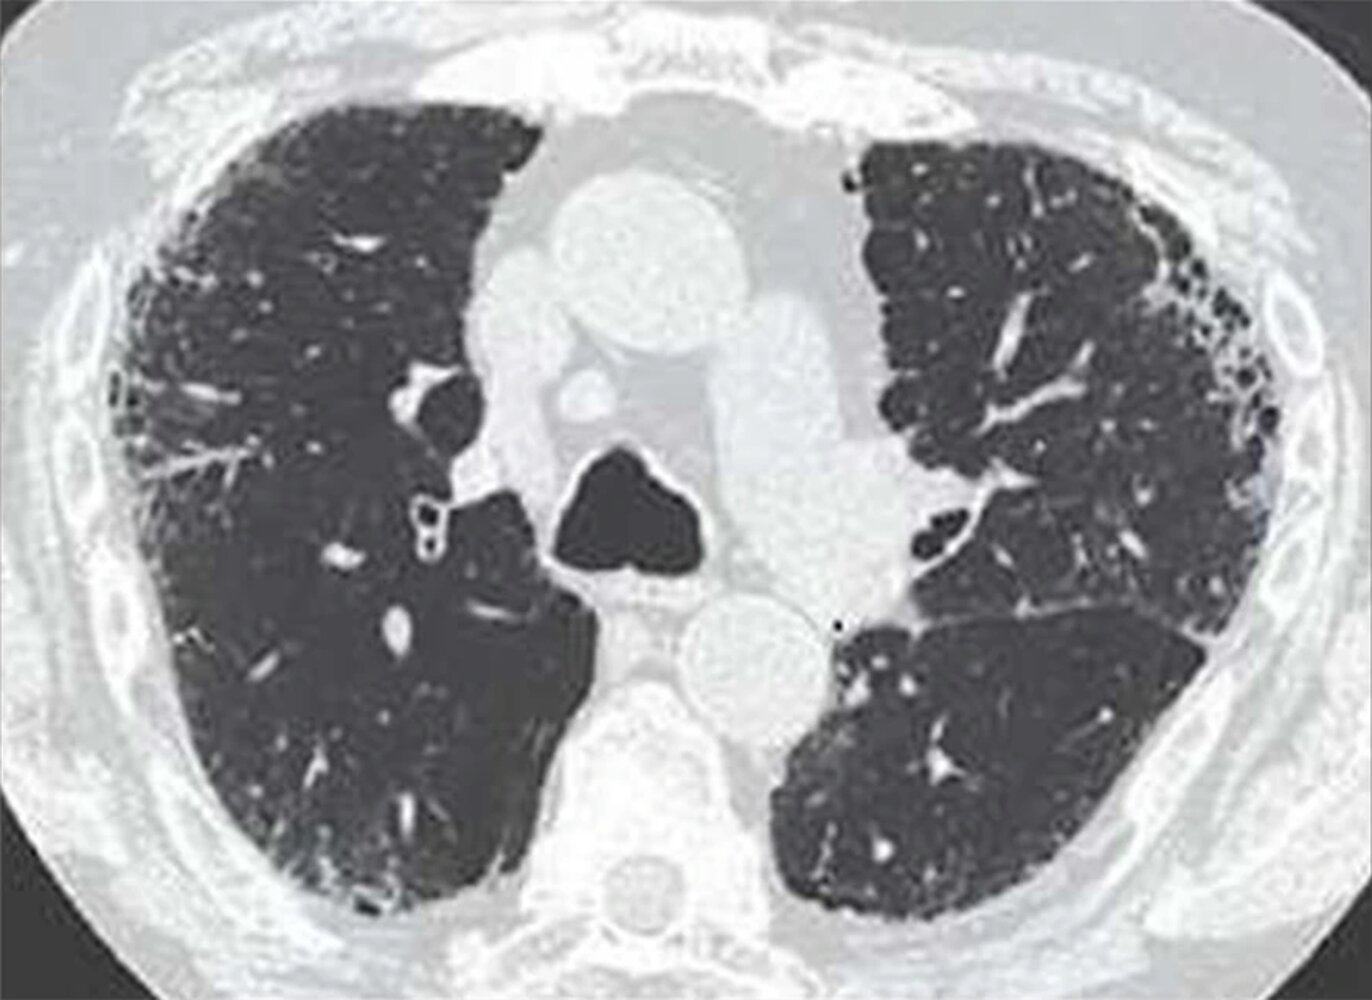

• HRCT

• Signs of interstitial fibrosis, e.g.:

• Subpleural linear opacities

• Septal and interlobular thickening

• Honeycombing

• Rounded atelectasis

• Pleural abnormalities

• Calcified (ivory white) or noncalcified pleural plaques

• Pleural reticulonodular opacities

• Pleural thickening